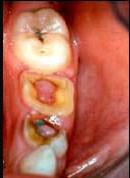

问题 临床上牙髓息肉一般见于()

选项 A.急性牙髓炎浆液期 B.急性牙髓炎化脓期 C.慢性闭锁性牙髓炎 D.慢性溃疡性牙髓炎 E.慢性增生性牙髓炎

答案 E